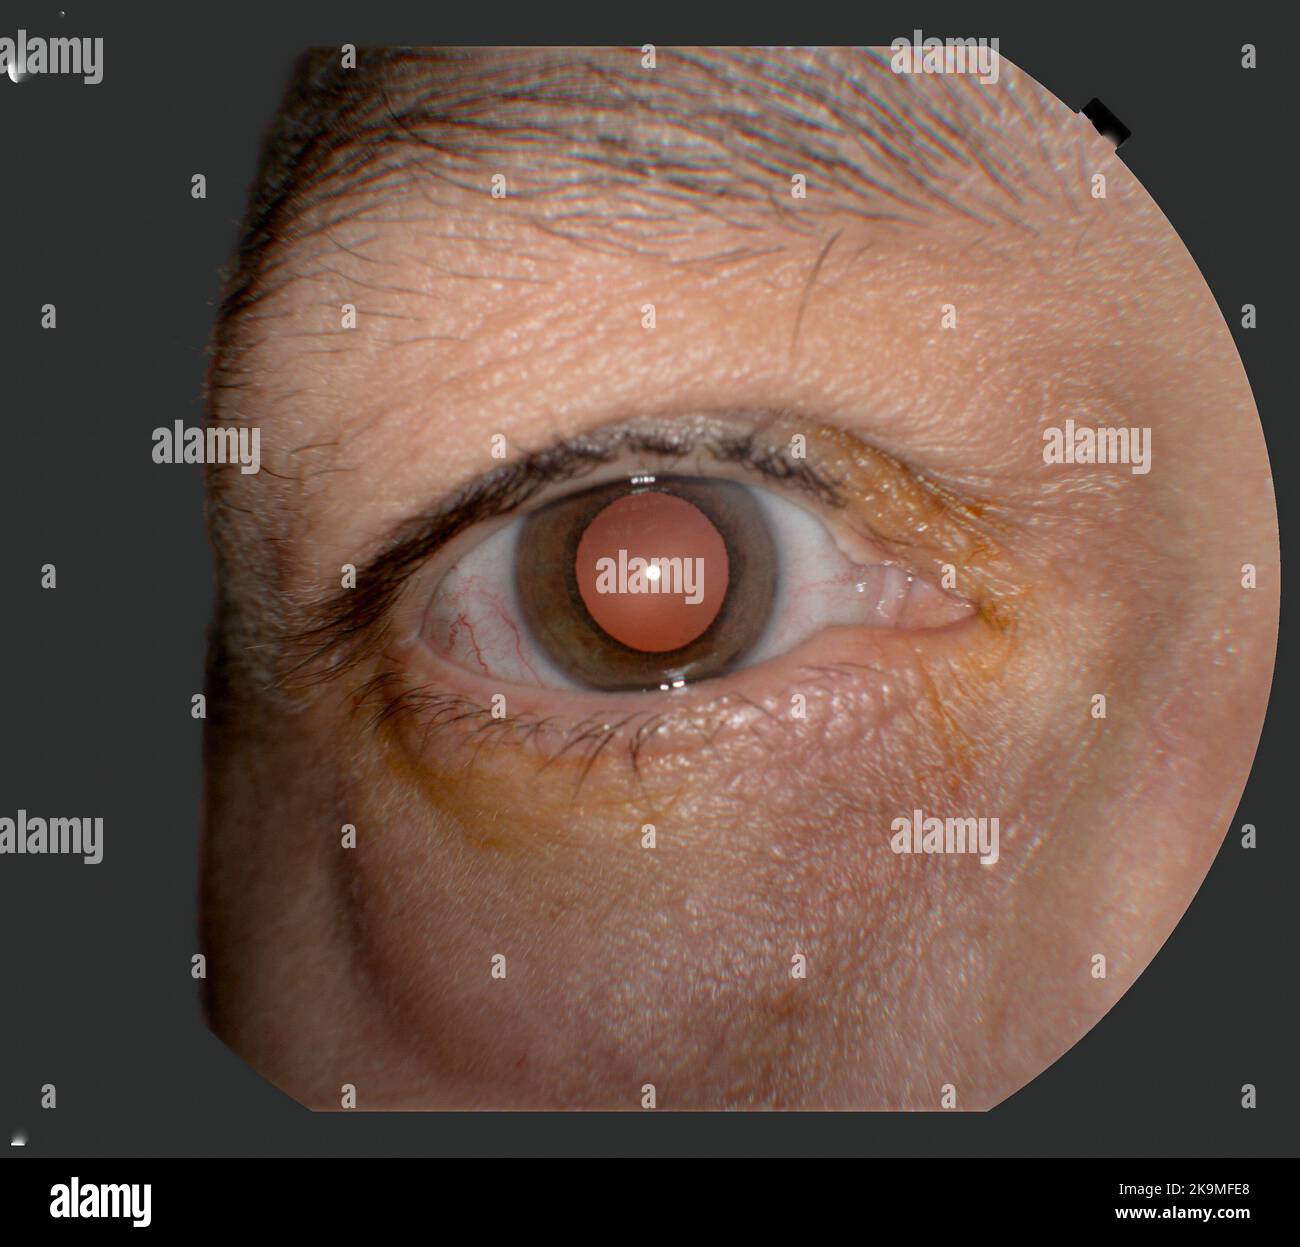

Photography of Human Eye Retina Stock Photohttps://www.alamy.com/image-license-details/?v=1https://www.alamy.com/photography-of-human-eye-retina-image487873457.html

Photography of Human Eye Retina Stock Photohttps://www.alamy.com/image-license-details/?v=1https://www.alamy.com/photography-of-human-eye-retina-image487873457.htmlRF2K9MFG1–Photography of Human Eye Retina

Photography of Human Eye Retina Stock Photohttps://www.alamy.com/image-license-details/?v=1https://www.alamy.com/photography-of-human-eye-retina-image487873408.html

Photography of Human Eye Retina Stock Photohttps://www.alamy.com/image-license-details/?v=1https://www.alamy.com/photography-of-human-eye-retina-image487873408.htmlRF2K9MFE8–Photography of Human Eye Retina

Photo of human eye anatomy Stock Photohttps://www.alamy.com/image-license-details/?v=1https://www.alamy.com/photo-of-human-eye-anatomy-image487942713.html

Photo of human eye anatomy Stock Photohttps://www.alamy.com/image-license-details/?v=1https://www.alamy.com/photo-of-human-eye-anatomy-image487942713.htmlRF2K9RKWD–Photo of human eye anatomy

View of Human eye up close Stock Photohttps://www.alamy.com/image-license-details/?v=1https://www.alamy.com/view-of-human-eye-up-close-image487942716.html

View of Human eye up close Stock Photohttps://www.alamy.com/image-license-details/?v=1https://www.alamy.com/view-of-human-eye-up-close-image487942716.htmlRF2K9RKWG–View of Human eye up close